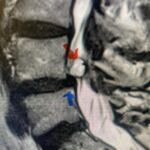

A 37-year-old male police officer complained of a one-month history of difficulty with his balance and leg weakness. He complained of achiness in his legs. He also complained of bilateral arm weakness and numbness of his hands. He was also having difficulty writing due to the weakness. Patient had an MRI of the cervical spine which demonstrated a disc/osteophyte at C56 causing spinal cord compression and concurrent myelomalacia (Fig. 3). Patient underwent an anterior cervical discectomy with a cage and plate (Fig. 4). He tolerated the procedure well with improved numbness and weakness. This is a young person with fairly extensive myelomalacia and a fairly rapid development of symptoms. For this it was felt surgery was indicated. How he will do will depend on how much of his symptoms was caused by the compressive component or intrinsic damage to the spinal cord. As a rule, patients generally improve to some extent quickly; but their recovery of their spinal cord function can sometimes take up to 2 years to realize the extent of their improvement. Patients have to be patient with themselves in terms of their expected recovery.